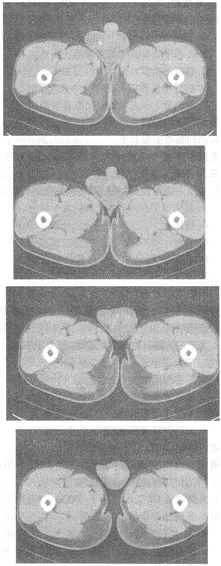

1.男,20歲,外傷1天,左側(cè)陰囊腫痛,結(jié)合CT平掃圖像,最可能的診斷是

正確答案:A 解題思路:陰囊腫大,左側(cè)睪丸結(jié)構(gòu)不清,可見弧形高密度影,內(nèi)見低密度區(qū),結(jié)合外傷病史,考慮睪丸血腫可能大。